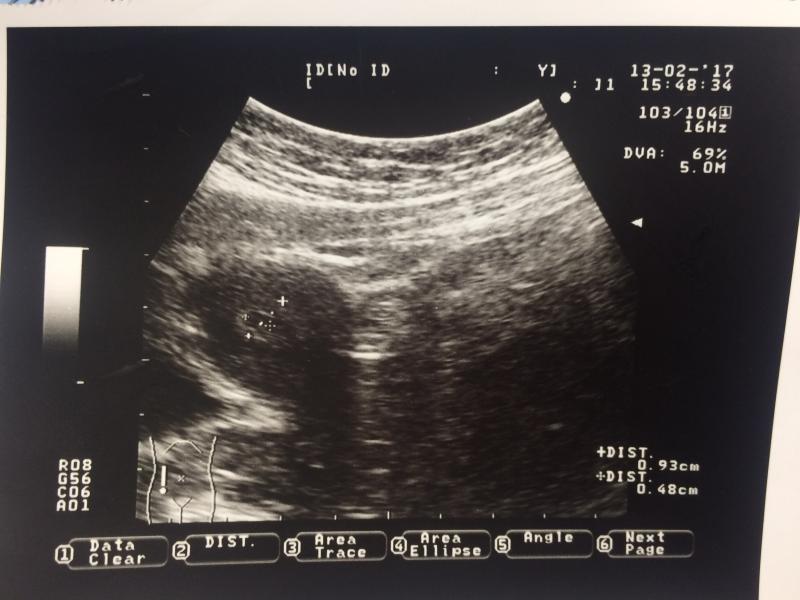

Сделала узи, сказали 2-3 недели, маточная беременность, ну почему то мне кажется что не видно почти, все хорошо?

Мне на вашем сроке и не делали)) на 6-ой недельки только показали сердечки обоих) а у вас видно) маточная это отлично! Теперь ждите сердечко

Всё видно! В следующий раз идите в 7недель, тогда уже забьется сердечко и вам будет спокойней 😊

@shermanma на вашем сроке то, что маточная беременность уже хорошо)) не переживайте.